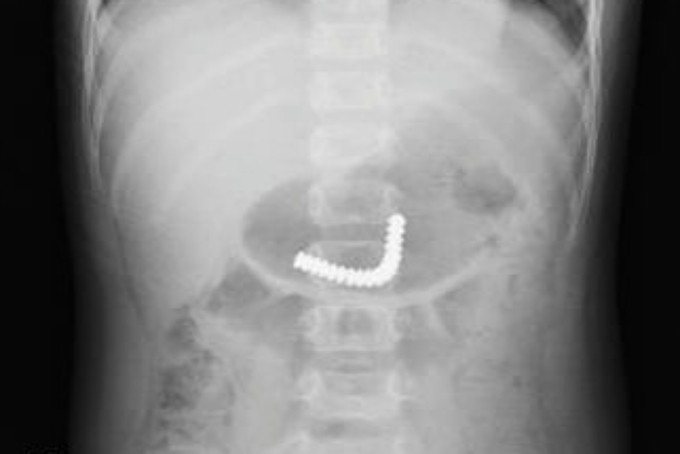

18 viên nam châm kết chùm trong ruột bé trai

Sáu giờ trước khi vào Bệnh viện Nhi đồng Thành phố hôm 21/12, bé cầm chơi rồi nuốt các nút nam châm này. Sau đó bé không đau bụng, không ói nhưng vô cùng hoảng loạn. Lúc này, các viên nam châm kết thành chùm, trôi xuống ruột non bé, bác sĩ phải mổ nội soi khẩn cấp để lấy ra.